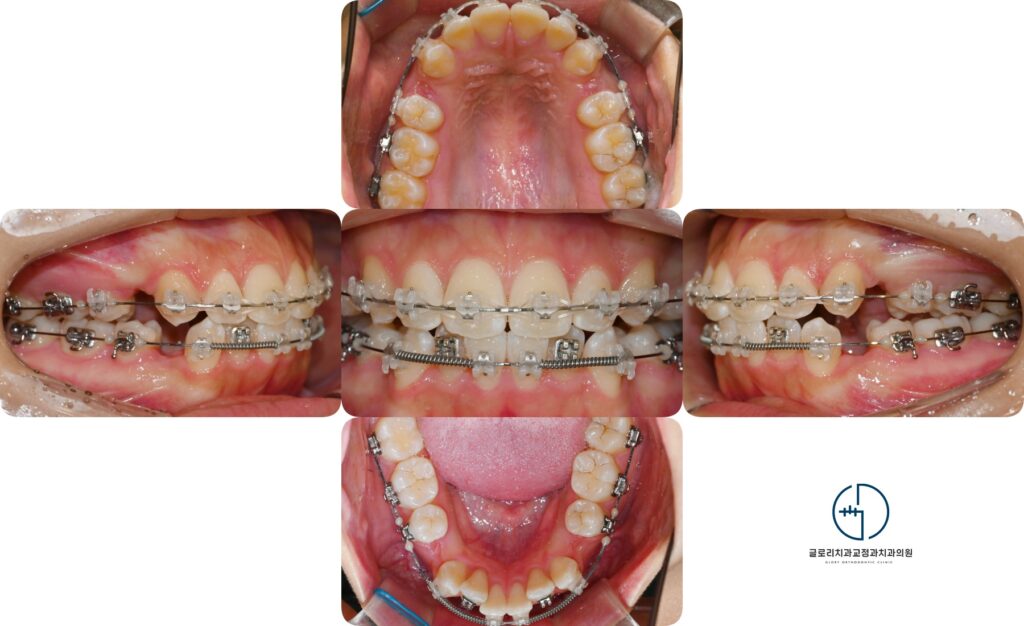

중랑구 교정치과 에서 보여드리는 자료를 보면 현재 전치부가 서로 겹쳐져있으며

일부 치아는 회전되어있거나 치열밖으로 벗어난 모습을 확인합니다.

또한 배열이 고르지 못하다 보니 칫솔이 잘닿지 않는 사각지대가 생기면서

이 주변으로 치석과 치태가 쌓인 모습도 관찰됩니다.

중랑구 교정치과 에서 보여드리는 사진을 보면 현재 치면에 장치가 부착되어 초기 배열이 시작되었음을 알 수 있습니다.

이번 케이스에서는 공간 확보를 위해 위아래 4개 소구치가 제거되었는데 이를 통해 돌출된 앞니를 후방으로

이동시킬 수 있는 공간이 마련되었습니다.

또한 총생으로 불규칙하게 자리잡고있던 치아들도 교정력으로 점차 배열될 수 있습니다.

초기 단계에서는 치아의 높낮이와 기울기를 맞추는 과정이 함께 이루어지며 이후 확보된

발치 공간을 활용해 점진적으로 후방으로 이동시키는 단계로 넘어가게 됩니다.

브라켓과 와이어는 자연치에 지속적이고 일정한 힘을 전달하는 역할을 합니다.

고무줄은 상하간의 교합 관계를 조절하고 앞뒤 균형을 맞추는데 도움을 주죠.

특히나 이번과 같이 골격성 2급 부정교합은 하악의 전후방 관계도 고려가 필요하기 때문에

고무줄을 사용해위아래 조화를 세밀하게 조절할 수 있습니다.

사진과 같이 전치부 쪽 고리에 고무줄을 걸어 어금니에 부착된 장치에 연결해주면

지속된 힘이 가해지면서 치아를 후방으로 유도하고 앞니의 기울기를 조정할 수 있습니다.

이 과정은 전치 돌출을 개선하고 상하의 균형을 맞추는 주요 단계로, 치료가 진행될수록

입술라인이 자연스럽게 후퇴하고 전체적인 얼굴 균형에 긍정된 변화를 가져올 수 있습니다.

서서히 이가 움직임에 따라 빈 공간이 닫히고 있으며 교합에 정밀함을 가하게 됩니다.